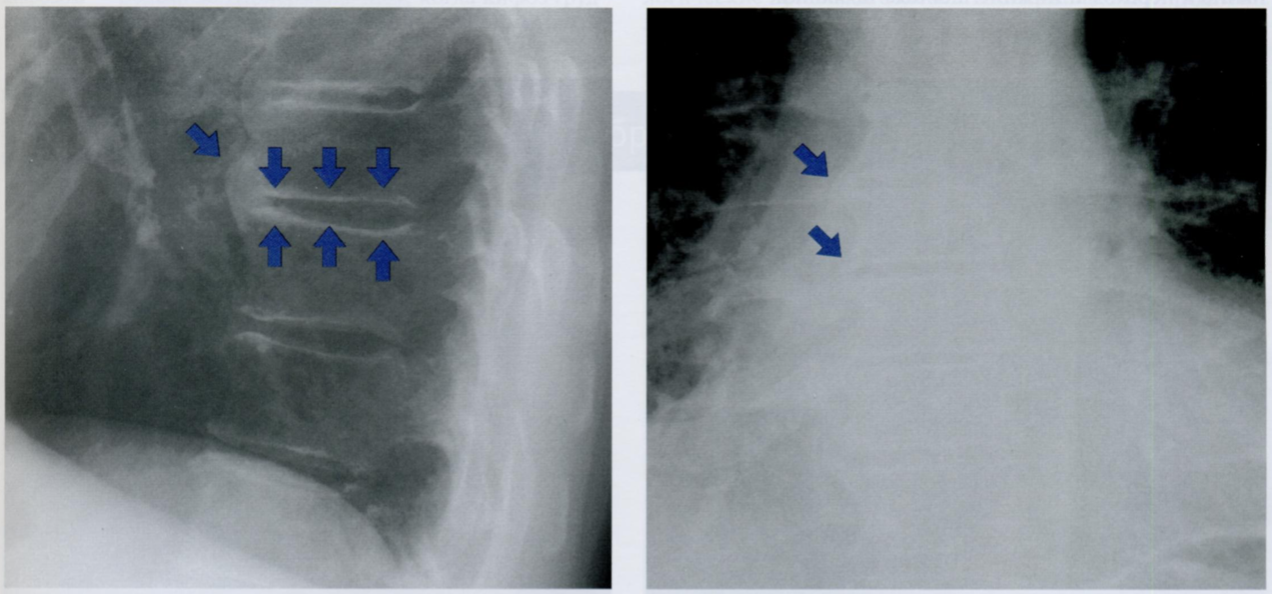

Данный снимок выполнен у одного и того же пожилого пациента с интервалом в 3 месяца. Обратите внимание на неравномерное утолщения ребер, отмеченные стрелками.

Дайте характеристику находке. Какие структуры грудной клетки наиболее часто поражаются?

Как отличить данную находку от костной мозоли после перелома?

Гематогенные метастазы - наиболее часто встречающиееся опухоли скелета грудной клетки у пожилых людей.

Особенно подозрительны кости, которые содержат костный мозг - ребра, грудина и позвоночник.

На повторном снимке мы видим прогрессию кортикального дефекта и увеличение размера метастаза.

На снимке слева ниже для сравнения показано веретенообразное утолщение после перелома ребра (костная мозоль), которое не сопровождается остеолическими изменениями кости. Важно визуально отличать костные мозоли и метастазы на ребрах.

На правом снимке также представлены участки остеолиза на телах грудных позвонков +/- снижение их высоты (отмечено стрелкой). При этом эти изменения не видны в ЗПП, поэтому показана БП.